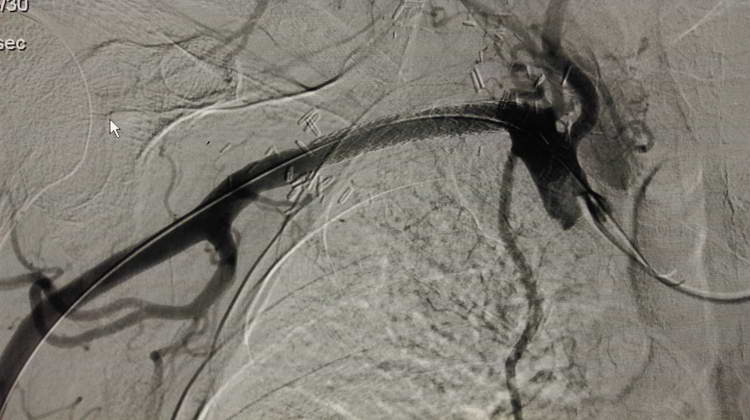

Аневризмы подключичной артерии Позиционирование стент-графта

07.10.15г. интервенционным кардиологом А. Цатуряном была проведена операция-селективная ангиография правой подключичной артерии. Через правый лучевой доступ был проведен стент-графт диаметром 8 мм, длиной 59 мм в подключичную артерию, который под ангиографичесикм контролем через бедренный доступ был имплантирован в сегменте аневризматических расширений. Стент-графт представляет собой обычный стент, который покрыт тефлоновой оболочкой и предназначен для лечения сосудистых перфораций и закрытия сосудистых аневризм.

При повторной ангиографии стент-графт полностью закрыл устья аневризм (что видно на фотоснимках). При этом кровоток в правой позвоночной и внутренней грудной артериях не был нарушен.

После имплантации стент-графта Субтракционная ангиография брахиоцефального ствола